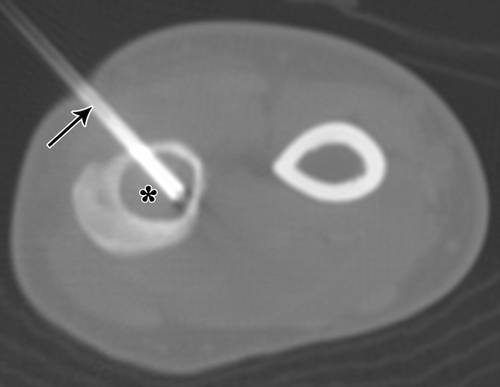

![]()

5 / 20岁女性桡骨内软骨瘤。

前臂的CT图像显示11号针头(箭头),桡骨(星号)。小心不要穿过骨间膜。